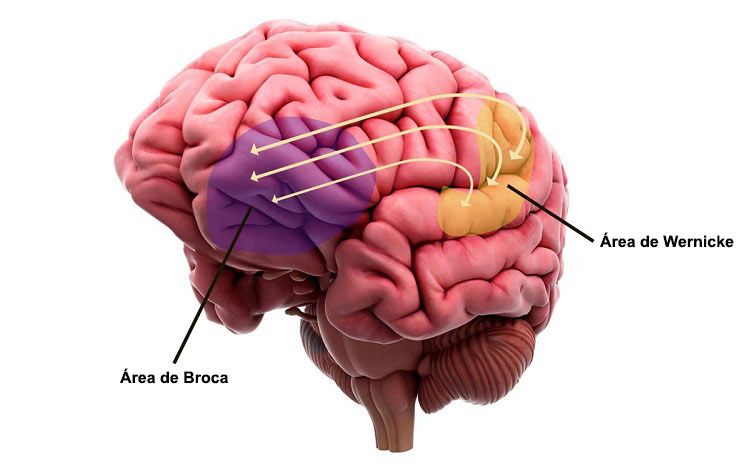

El área de Broca ubicada en la tercera circunvolución frontal (en el lóbulo frontal) del hemisferio cerebral izquierdo, si bien en algunos casos excepcionales se encuentra en el hemisferio derecho. Concretamente, según el mapa de Brodmann, ocupa las áreas 44 y 45 de Brodmann, cerca del ojo y pegado a la parte frontal del lóbulo temporal.

Este síndrome se distingue especialmente de otro tipo de afasia relacionada con una parte del cerebro llamada área de Wernicke. Se trata de la afasia de Wernicke, en la que, en comparación a la afasia de Broca, el lenguaje y la escritura son mucho más fluidos, pero se pierde la capacidad de dotar de significado a lo que se dice o a lo que se lee o escucha, por lo cual no se entiende lo que dicen otros.